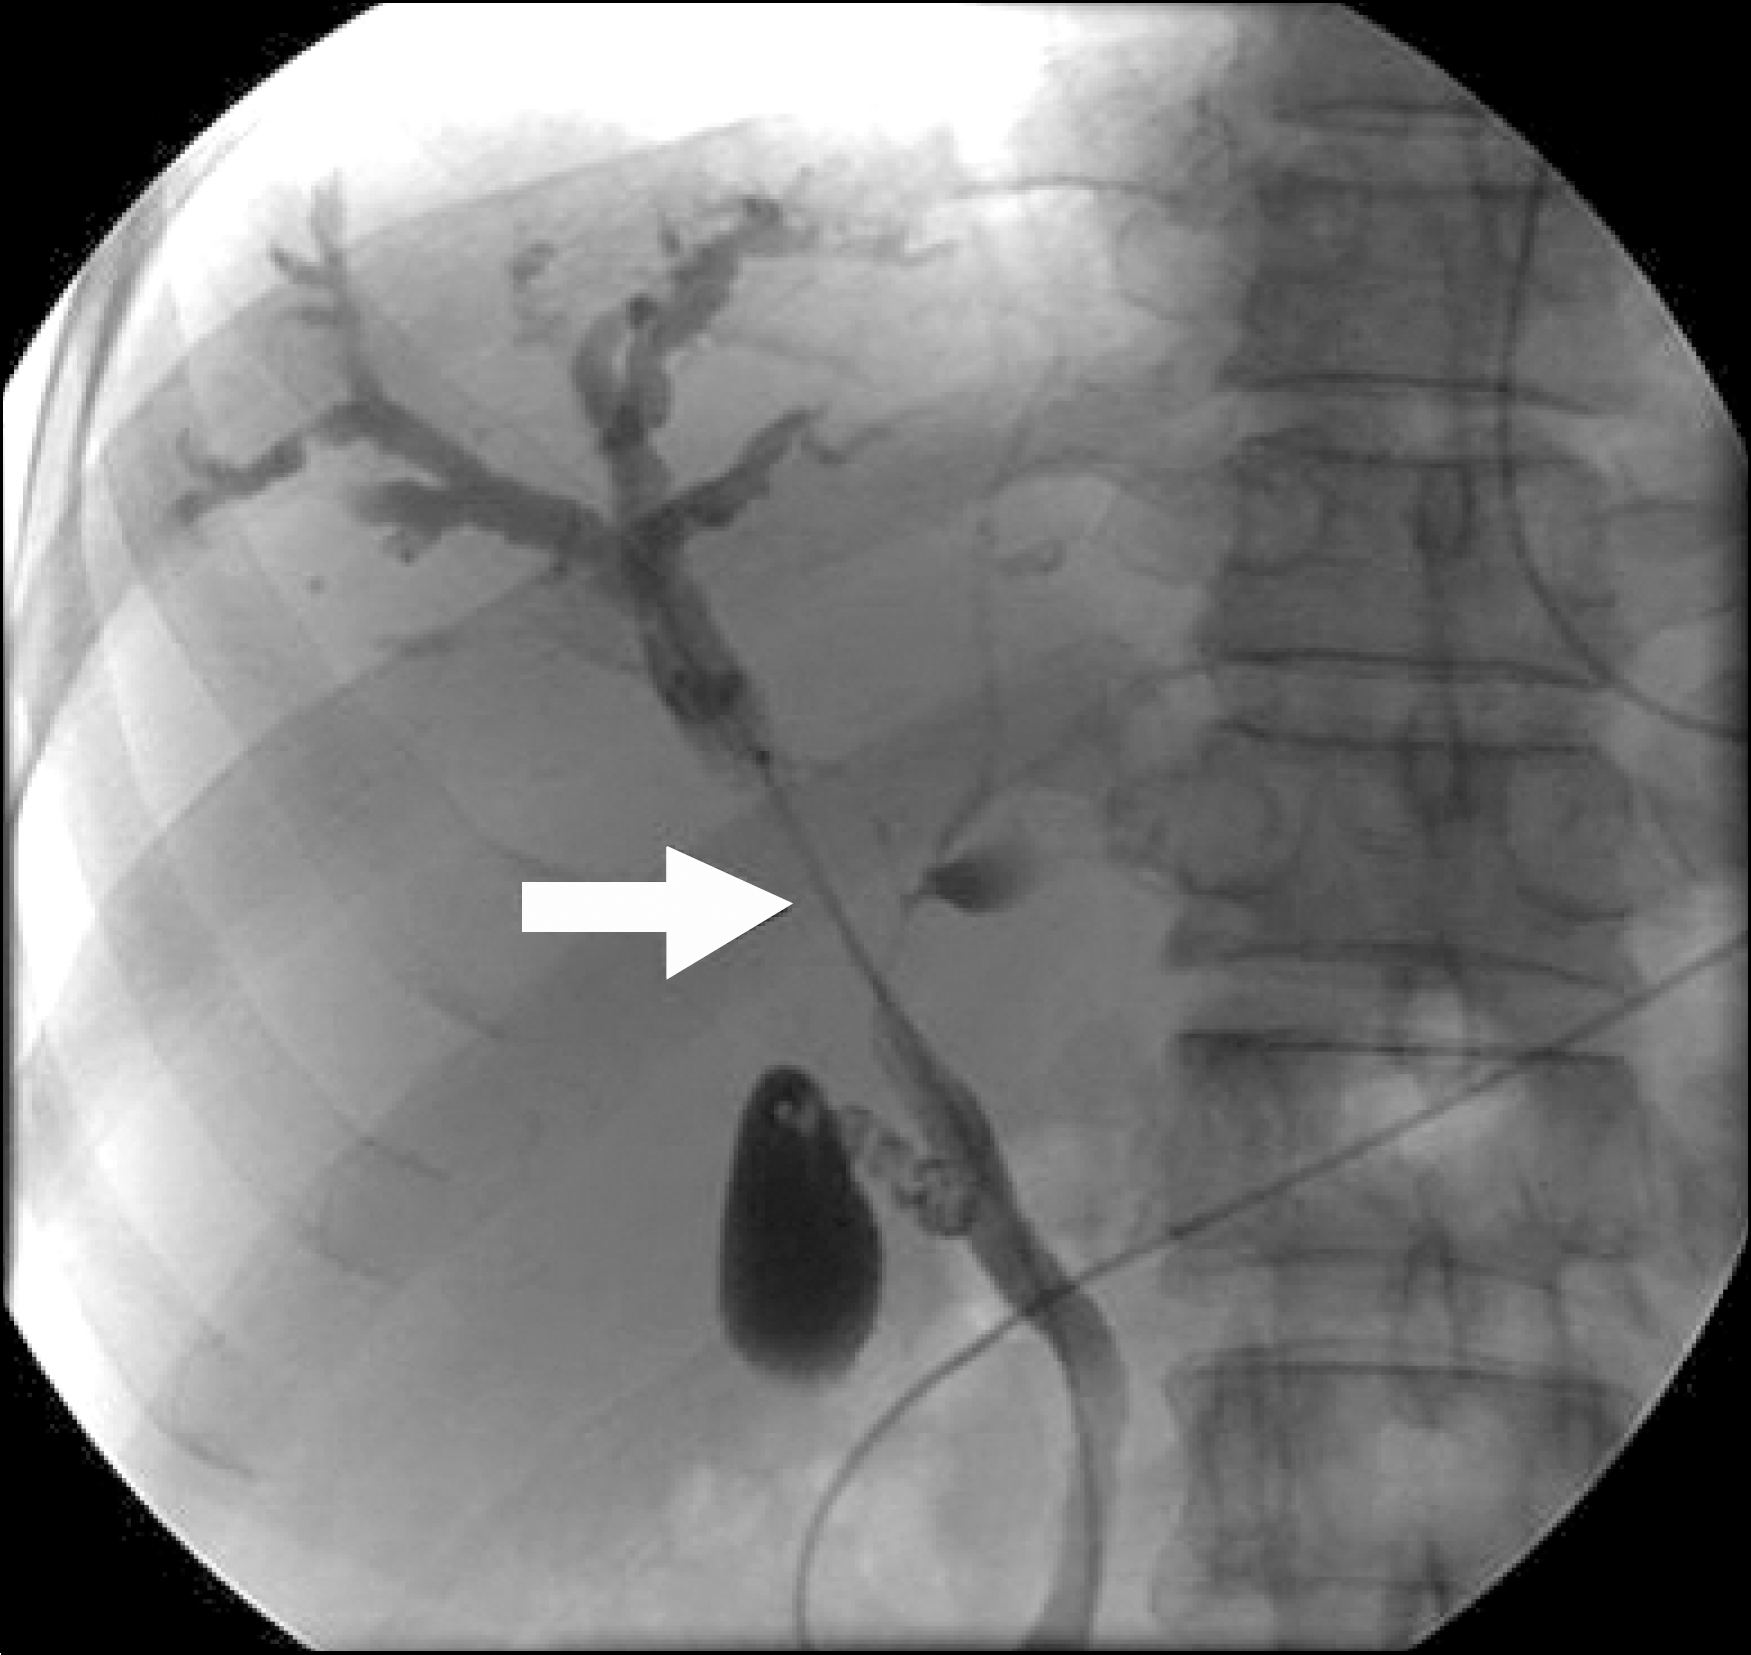

Fig. 2.

Magnetic resonance cholangiopancreatography (MRCP) showed stenosis of the main hepatic duct junction (arrow) with dilatation of intrahepatic bile ducts.